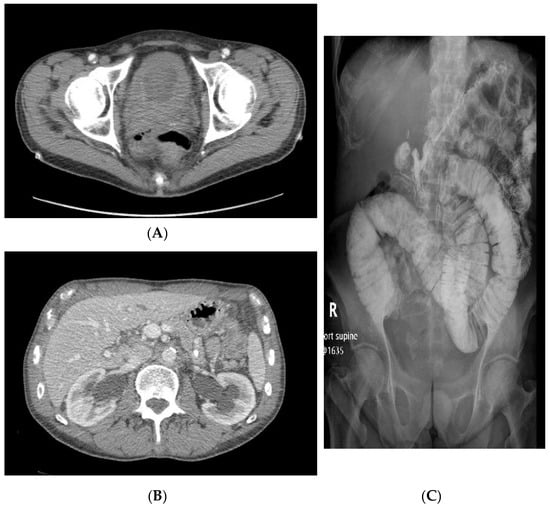

2. Case Series